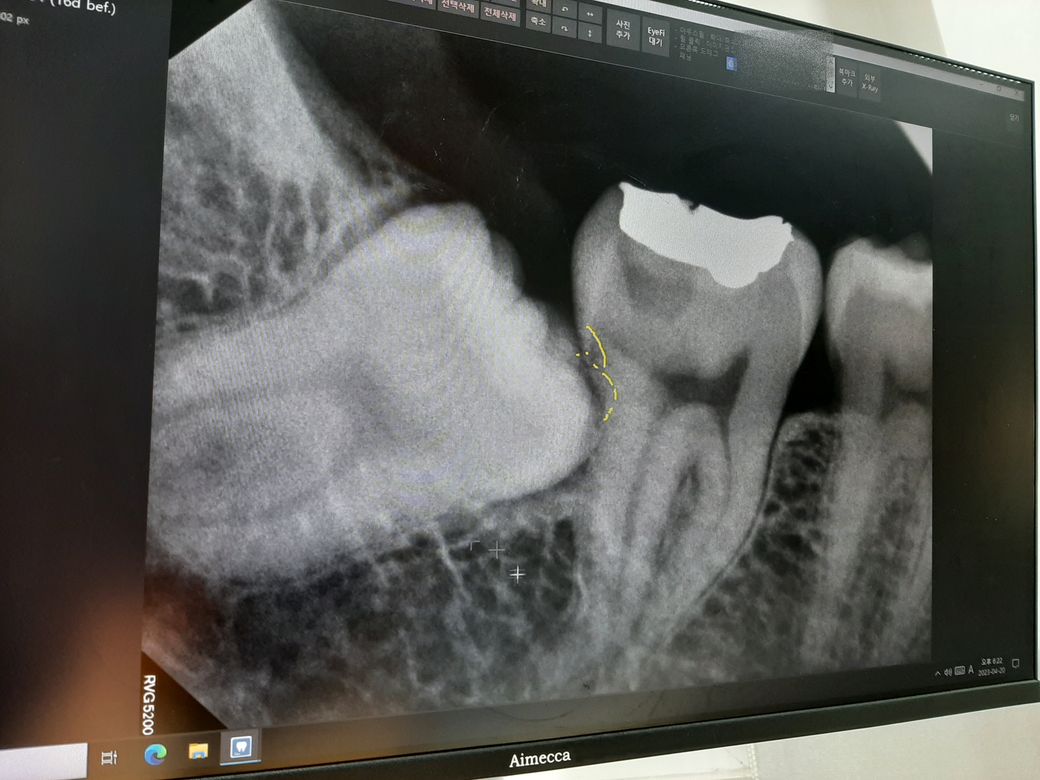

오른쪽 아래 사랑니

1. 아래 사랑니와 어금니 사이의 인접한 부분에 검은색 선 같은게 있는데 이게 공간이 빈 거라고 설명해주셨습니다만 썩은 건가요?

1. 충치가 아닌 잇몸 염증이 경미하게 있는 것으로 보입니다.

-저부위는 사랑니 발치를 하고 나서 확인을 해보시는게 정확합니다. 사진상으로 보면 충치가 잇어 보이진 않습니다.